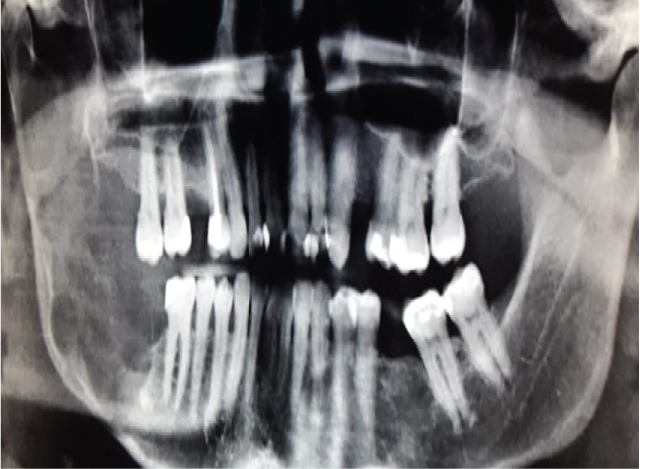

The latest World Health Organization classification of Tumours of the Head and Neck (2017) reevaluated the concepts on the clinical, radiological and biological features of the Keratocystic Odontogenic Tumor (KCOT) and has decided to rename this lesion to Odontogenic Keratocyst again (OKC) [1]. The motivation for this policy change, however, is lacking. The OKC is potentially a very aggressive lesion (Figure 1) and this name change may bring about some confusion among surgeons and tends to lessen the alertness among surgeons to treat this lesion adequately [2].

Figure 1: Large OKC in the right posterior region of the mandible demonstrating its aggressiveness. View Figure 1

OKC's grow in the medullary space of the mandible or maxilla with no or little expansion of the cortical bone [1,3]. Thus, initial, small lesions are usually asymptomatic unless they get infected [18]. However, if the cyst perforates thinner regions of the cortical bone, from the inside to the outside, a local swelling may take place (Figure 2). This happens often with regular, ordinary, odontogenic cysts, e.g. radicular or dentigerous cyst. Suddenly, patients may develop trismus in case of larger OKC's in the mandibular ramus (Figure 1). Larger OKC's in the maxilla may expand into the maxillary sinus (Figure 3) and cause nasal obstruction on the same side. On the other hand, slow growing cysts may stimulate periosteal bone apposition and cause bone expansion without cortical perforation. OKC's occur over a wide patient age range, most commonly in the posterior region of the mandible of men in the second to third decades of life [26].